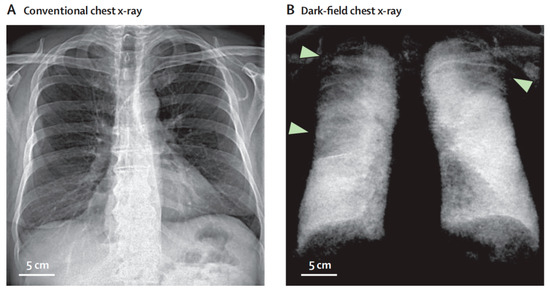

- Willer, K.; Fingerle, A.A.; Noichl, W.; Marco, D.F.; Frank, M.; Urban, T.; Schick, R.; Gustschin, A.; Gleich, B.; Herzen, J.; et al. X-ray dark-field chest imaging for detection and quantification of emphysema in patients with chronic obstructive pulmonary disease: A diagnostic accuracy study. Lancet Digit. Health 2021, 3, e733–e744. [Google Scholar] [CrossRef]